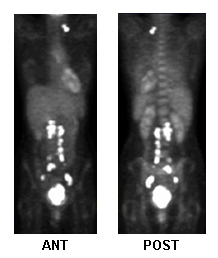

TEP con fluorodesoxiglucosa para la planificación del tratamiento, actividad metastásica

De la colección de Neil S. Horowitz, MD; utilizado con permiso

Ver esta imagen en el contexto de la/s siguiente/s sección/es: